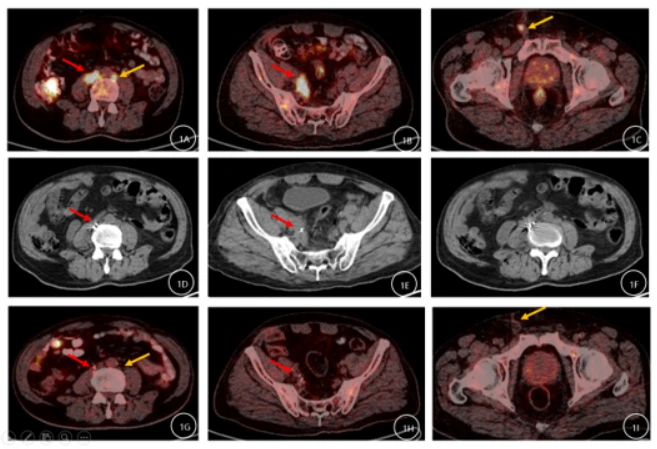

在本治疗中,放射性粒子术后我们对患者进行了为期近36个月的随访观察。2023年1月17日,患者接受了PET-CT(显像剂为FDG),结果显示原腹膜后及右侧盆腔部分淋巴结已消失,残存淋巴结较前缩小,FDG代谢较前明显减低(图1G-I)。2024年5月09日行泌尿系CT示:未见肿瘤明显复发或转移表现(图2)。2025年6月03日行泌尿系CT示:未见肿瘤明显复发或转移表现(图3)。2025年9月05日行泌尿系CT示:未见肿瘤明显复发或转移表现(图4)。随访期间仅行免疫治疗。通过这些检查结果,我们可以得出结论,在单纯免疫治疗效果不佳情况下,125I粒子植入治疗联合免疫治疗在该患者中显示出了良好的疗效。在长达3年的随访中,转移淋巴结的代谢活性降低和体积缩小,代谢活性明显降低甚至消失,尤其是未行放射性粒子治疗的转移灶,且未见新发转移灶,均表明治疗策略的有效性。这些发现为转移性尿路上皮癌的治疗提供了有价值的参考。

图2:2024年5月09日行泌尿系CT示:未见肿瘤明显复发或转移表现